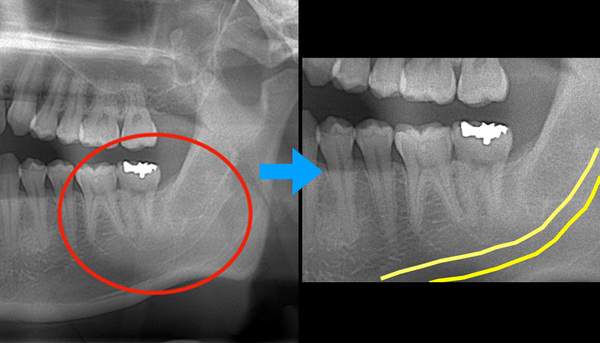

そのため当院では、2次元のレントゲンで親知らずと下歯槽神経の位置が近い場合は、3次元のレントゲンである、CTを撮影します。それによって、親知らずと下歯槽神経の位置関係をしっかりと把握し、また、根の形もみて、いきます。そうすることで、抜歯をする前から抜くためのシュミレーションをしておくことができますので、手術時間の短縮にもつながります。

そのため、抜くことをお勧めしていますが、レントゲン写真で、下歯槽神経と親知らずが近接していることが確認できます。

麻布十番歯科で抜歯予定の親知らずの生え方を確認するためのレントゲン写真

CTの画像です。下歯槽神経と親知らずはほんの少し接触していることがわかります。そのため、この親知らずは2回に分けて抜いていくことにしました。1回目は歯の頭の部分だけを切るだけになります。2回目は1−3ヶ月経ってから行います。

1回目で頭の部分を取ったスペースに歯が伸びてきますので、下歯槽神経と離れたかどうかを再びCTで確認して、残りの根の部分を抜いていく方法になります。